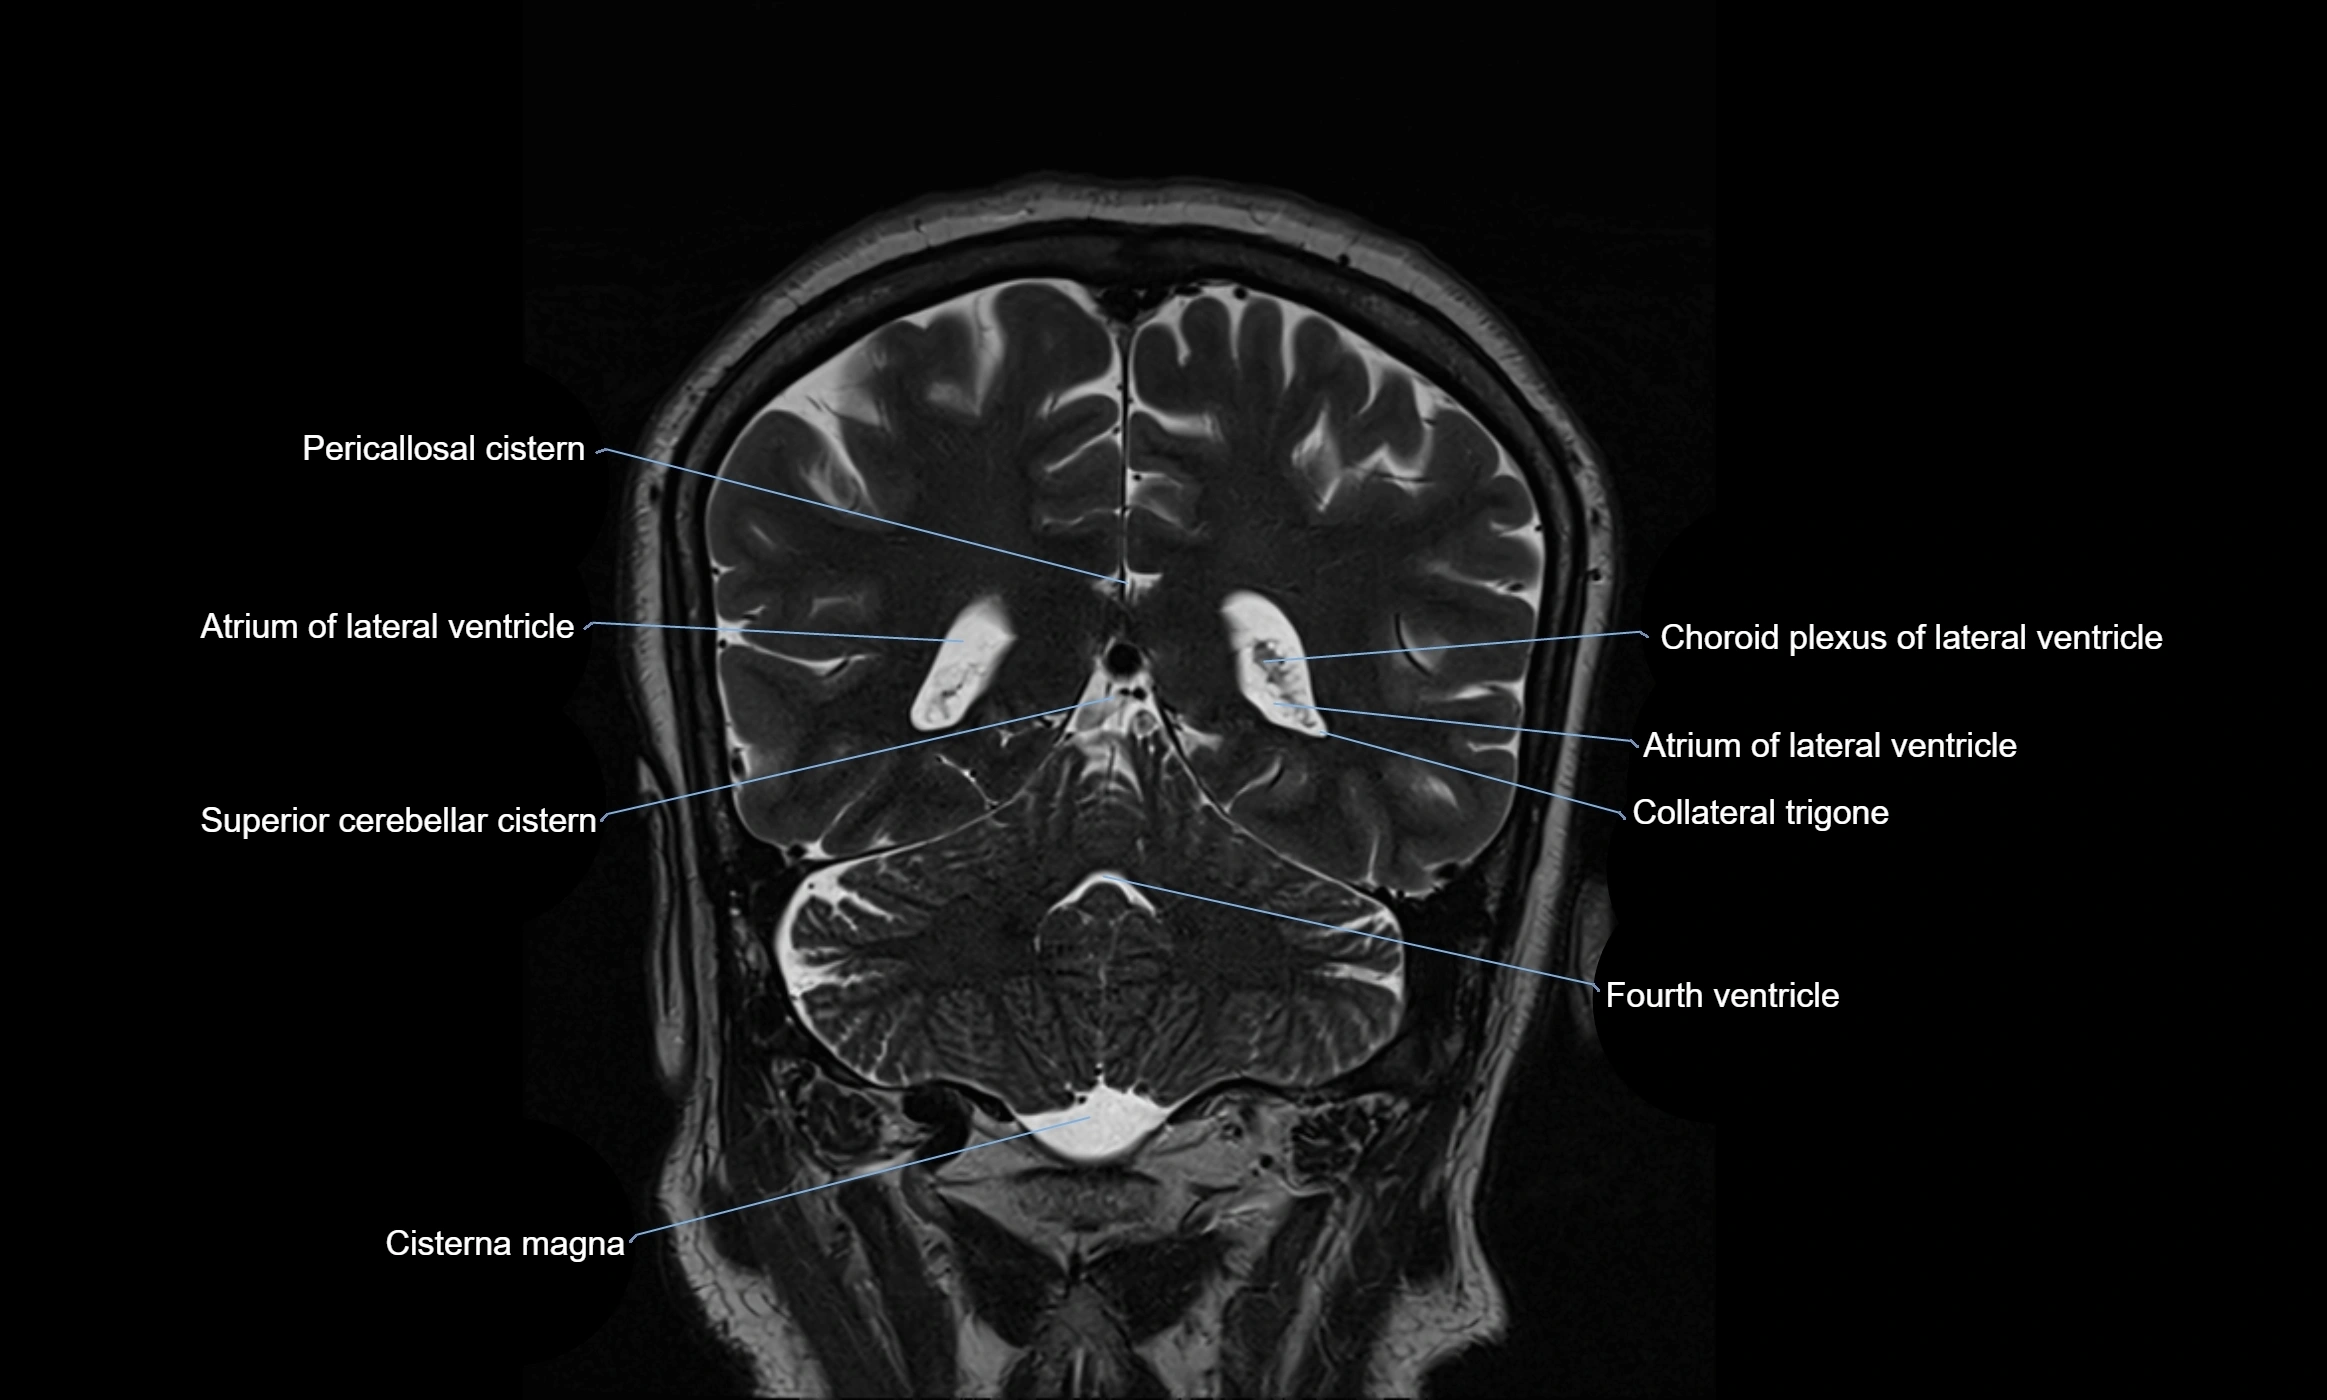

CT image

image